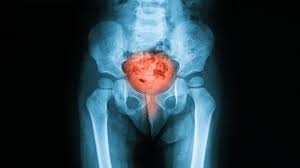

How Do U Know U Have Bladder Cancer : Bladder Cancer World Cancer Research Fund International : A biopsy is a procedure in which a doctor takes a tissue sample from the area where cancer may exist.. The majority of people have bladder cancer that hasn't invaded the muscle wall when first diagnosed. Here you can find out all about bladder cancer, including risk factors, symptoms, how it's found, and how it's treated. If you have bladder cancer or are close to someone who does, knowing what to expect can help you cope. If you have stage 1a endometrial cancer and still want to have children, you may be able to use progestin therapy. Bladder cancer can also be signaled by an abrupt and unintentional loss of weight, and swelling in the legs.

Age (it typically occurs in people over 55) gender (bladder cancer is far more common in men) a history of tobacco use (current or past tobacco use, along with blood in your urine is a worrisome combination) To find out whether you have bladder cancer, the first thing your doctor probably will do is a complete medical history. Inexplicable pain in your pelvis can be a sign of bladder cancer, as can bone pain in and around your groin. In some cases, you can't see blood in your urine. When symptoms of bladder cancer do occur, they include:

Here you can find out all about bladder cancer, including risk factors, symptoms, how it's found, and how it's treated. The majority of people have bladder cancer that hasn't invaded the muscle wall when first diagnosed. There may be a sense of needing to urinate frequently (urinary frequency) or having to urinate urgently ( urinary urgency ). Blood in the urine in most cases, blood in the urine (called hematuria) is the first sign of bladder cancer. Bladder cancer ُearly symptoms bladder cancer affects 68,000 adults in the united states each year. This is needed to know for sure if you have bladder cancer. They'll ask you about your overall health, as well as anything that. More than one sample may be taken because sometimes cancer starts in more than one part of the bladder. Bladder cancer can also be signaled by an abrupt and unintentional loss of weight, and swelling in the legs. Burning when trying to urinate. It has not invaded (spread deeper into) the bladder wall. In some cases, you can't see blood in your urine. Blood in the urine (hematuria).

Tests and procedures used to diagnose bladder cancer may include: Sometimes symptoms are linked to certain cancer types. If you have disease, diseased cells will be there too, says. It's easy for women to overlook because it's typically painless and can go weeks or even months between occurrences. But signs can also be more general, including weight loss, tiredness (fatigue) or unexplained pain. Blood in urine (hematuria), which may cause urine to appear bright red or cola colored, though sometimes the urine appears normal and blood is detected on a lab test Other problems affecting the bladder may also have an effect on the risk. How do you know if you have cancer? To perform cystoscopy, your doctor inserts a small, narrow tube (cystoscope) through your urethra. When symptoms of bladder cancer do occur, they include: Risk factors for bladder cancer include: Sounds iike i am in a very similar situation to where you were. In either case, the cancer is only in the inner lining layer of the bladder.